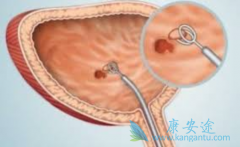

近些年来, 膀胱癌 在我国的发病率一直居高不下,其治疗也受到高度关注。临床上,时常可以看到一些膀胱癌患者因得不到及时、有效的治疗而导致病情延误,更有甚者因过度积极的杀伤性治疗而加重痛苦,缩短生命。就算病情得到暂时缓解,膀胱癌复发率也是很 ...

膀胱癌是指发生在膀胱黏膜上的恶性肿瘤,通常表现为无痛性、间歇性、肉眼全程血尿,有时也可为镜下血尿。膀胱癌是生活中一种常见癌症,那么 膀胱癌的早期症状 都有哪些呢?1、尿频尿急:肿瘤细胞侵犯膀胱三角区,就会刺激到膀胱,也可以及时发现膀胱癌的 ...